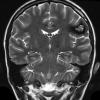

VASCULAR

Cavernous Angioma (10)